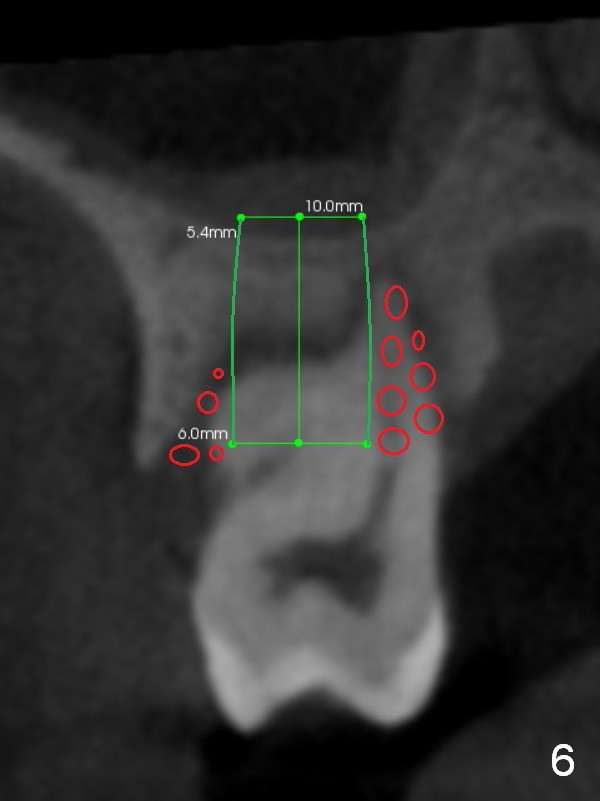

The socket is wider buccopalatally (Fig.2 (3-D disto-occlusal view),3 (coronal section)) than mesiodistally (Fig.1,4 (sagittal section),5 (axial section)). Unless more bone loss has occurred in the last year, a 6x10 mm UF implant is to be placed in the middle of the socket (Fig.6, (soaked with 2% Xylocaine/1:50,000 Epinephrine gauze)) with bone graft to be placed in the buccal and palatal gaps (red circles). Bone density in the middle of the socket is 550-700 Hounsfield units. Use RT2 or 2 mm pilot drill to start osteotomy ~ 3 mm. The largest osteotome is RT4, or largest reamer 4 mm, followed by 4.5x17 mm tap at 14 mm, until 6x17 mm one. Make sure that the sinus floor is penetrated.